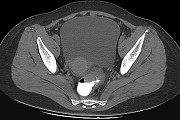

- 单项选择题男,67岁, 排便习惯改变,血便三个月入院, CT检查如图所示,下列说法错误的是  (    )

- A、直肠肠腔局限性增厚

- B、其表面欠光整,边界欠清晰

- C、可做直肠指检及活检以确定病变性质

- D、此为直肠息肉

- E、此为直肠癌